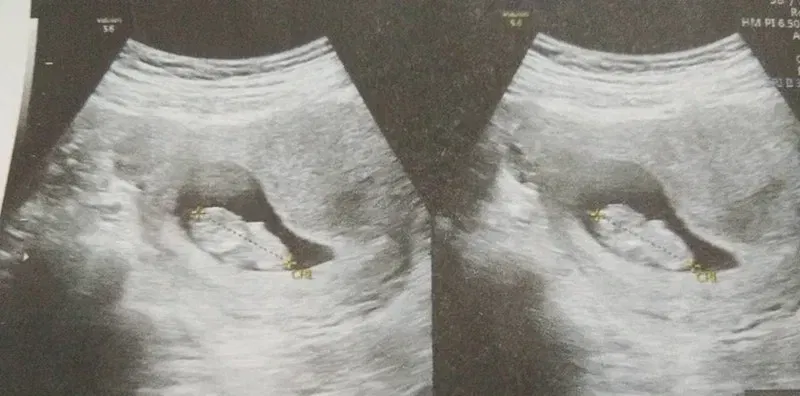

อย่าเพิกเฉยเพราะอาจเป็นสัญญาณของการแท้งลูกนะคะ >>>>